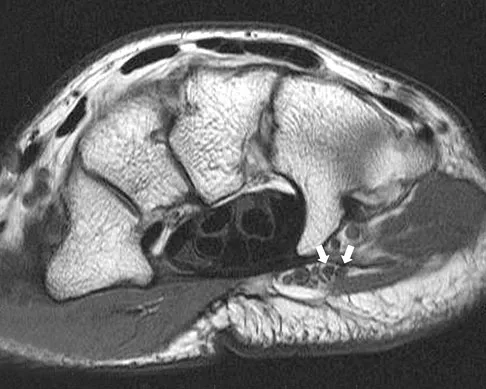

Figure 15a shows the radiograph of a patient who has a chondrosarcoma of the acetabulum. Bone scans are shown in Figures 15b and 15c. Numerous soft subcutaneous masses are present. A clinical photograph of the hand is shown in Figure 15d. What is the most likely diagnosis?

Explanation

Chondrosarcomas associated with diffuse bone lesions (enchondromas) are characteristic of Ollier's disease. When accompanied by subcutaneous masses (hemangiomas), the condition is called Maffucci's syndrome. Multiple hereditary exostosis is characterized by diffuse osteochondromas. McCune-Albright syndrome is characterized by polyostotic fibrous dysplasia with cafe-au-lait spots and precocious puberty. Neurofibromatosis can have associated bone lesions but is not associated with chondrosarcomas. Sun TC, Swee TC: Chondrosarcoma in Maffucci's syndrome. J Bone Joint Surg Am 1985;67:1214-1219. Schwartz HS, Zimmerman NB, Simon MA, et al: The malignant potential of enchondromatosis. J Bone Joint Surg Am 1987;69:269-274.